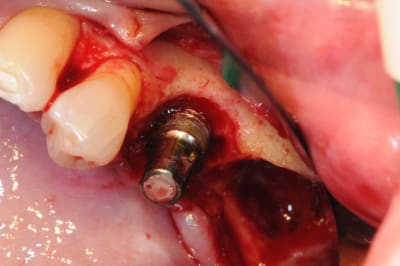

3 aspect (in vivo)

4 après un long moment de nettoyage, de curetage, de surfaçage implantaire, d'aeropolissage de l'implant, etc...

on fini enfin par arriver à ça.

2-3 l'implant 35 que j'ai décidé de garder et donc de nettoyer.

pour le nettoyage, j'ai utilisé, en plus de l'aéropolissage, un écouvillons de chez STRAUMANN en titane.(à mon avis beaucoup trop souple et trop long.